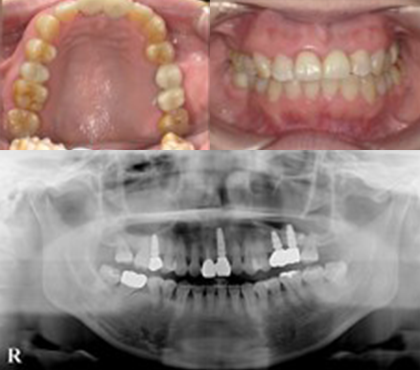

症例

奥歯は欠損放置による骨量不足のため骨増生を行い、前歯は破折歯をジルコニアセラミックとインプラントで補綴しました。前歯4本はオールセラミックにて修復しています。

| 治療費用 |

インプラント 1本 385,000円×4本 オールセラミック 1本 130,000 円×1本 骨増生 55,000円 |